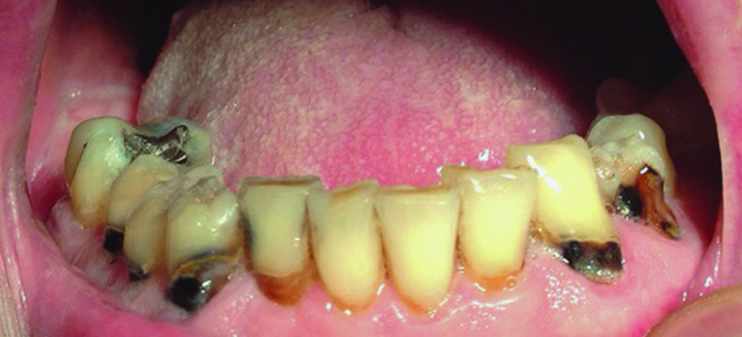

Dental caries, both new and recurrent, is also a frequently occurring infection resulting from lack of saliva. Older adults are particularly vulnerable because many have a greater number of retained natural teeth, previously restored dental surfaces, and gingival recession.11 Recurrent carious lesions are seen particularly in the buccal surfaces of previously restored anterior teeth and in incisal margins4 (Figure 1). Without proper salivary flow to restore the oral pH levels and to regulate bacterial populations, the oral cavity is rapidly colonized with caries-associated microorganisms.11 In regard to periodontal disease, the evidence in the literature is conflicting as to whether individuals with xerostomia are at an increased risk for periodontal disease. Some studies26-31 showed that the periodontal condition of individuals with Sjögren’s syndrome is similar to control individuals, whereas others demonstrated that these patients may have a worse periodontal condition compared to controls.32-34 These studies attributed the poorer periodontal conditions observed in individuals with xerostomia to the decrease in the amount of saliva and, consequently, the increase in plaque.35

Fig 1. Patient with rampant buccal/cervical caries due to long-term use of anticholinergic drugs.